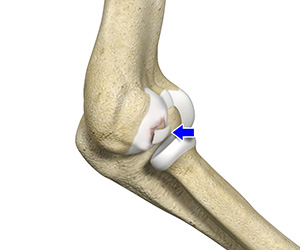

Elbow Instability

Elbow instability is a condition in which the elbow joint occasionally slides out of alignment due to the unstable state of the joint.

Elbow dislocation

Elbow dislocations usually occur when you fall onto an outstretched hand.